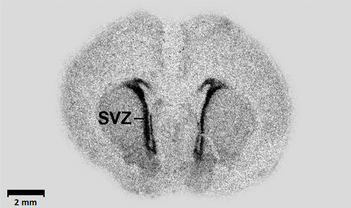

Autoradiograph, radyoaktif işaretli molekül veya yapıların yerini gösteren fotoğrafik bir görüntüdür. Otoradyografi tekniği kullanılarak elde edilir ve biyoloji, moleküler biyoloji gibi alanlarda besin alımı, DNA analizi gibi süreçlerde kullanılır.123

Makroautoradyografi (tüm organizma) ve mikroautoradyografi (hücre altı yapılar) olmak üzere iki türü bulunur. Radyoaktif izotoplarla etiketlenen moleküller, film veya jel üzerine yerleştirilerek görüntülenir.34